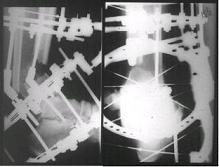

Огнестрельный дефект костей и передней группы мышц, поступил с

юнилатеральным аппаратом, стабильность плохая, из раны обильное гнойное

отделяемое. #1;#2. Стержневой апп. снят, наложен апп. Илизарова, дренажно